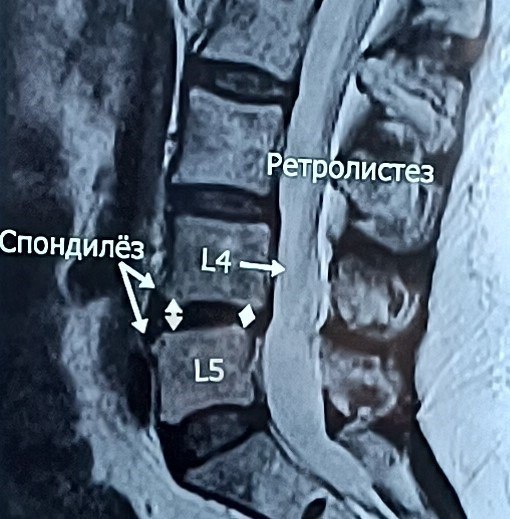

? Когда болит спина, мы привыкли винить во всем грыжу. Но часто МРТ открывает куда более глубокую картину, объясняя, почему стандартные упражнения не помогают, а боль становится хронической. МРТ — это золотой стандарт, который позволяет заглянуть внутрь и выстроить точный план спасения вашего позвоночника. Что же скрывается за снимками, кроме сухих цифр? ☑️ Жизнеспособность грыжи. Я смотрю не только на её размер, но и на структуру. На специальных режимах (STIR) видно, «светлая» грыжа или «темная». Светлая дает отличные шансы на резорбцию — её уменьшение без операции. Темная или застарелая требует уже другого подхода. ☑️ Скрытое воспаление (Модик 1). Бывает, что костные пластинки позвонков воспалены. Это та самая боль, которую невозможно «перетерпеть» или «закачать» в зале. ☑️ Состояние суставов Фасеточные суставы могут страдать от артроза или острого артрита. Это меняет всю биомеханику движения. ☑️ Костные «крючки» (остеофиты). Эти разрастания могут механически раздражать мышцы и